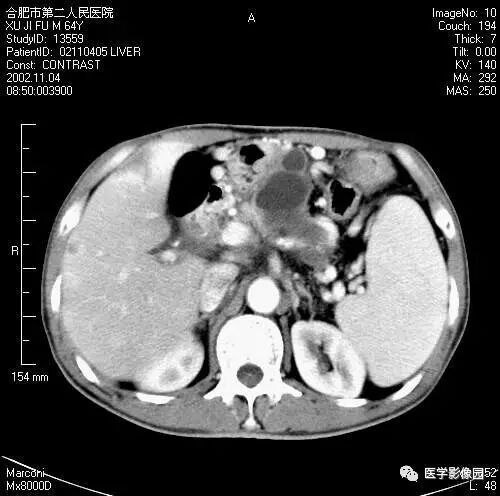

图6-4-9胰腺癌

A.CT平扫见胰头等密度肿块,

钩突明显圆隆;

B.增强扫描动脉期钩突内见境界

不清低密度灶(↑);

C.胰头部可见扩张的胆总管(↑)和

主胰管(长↑),即双管征